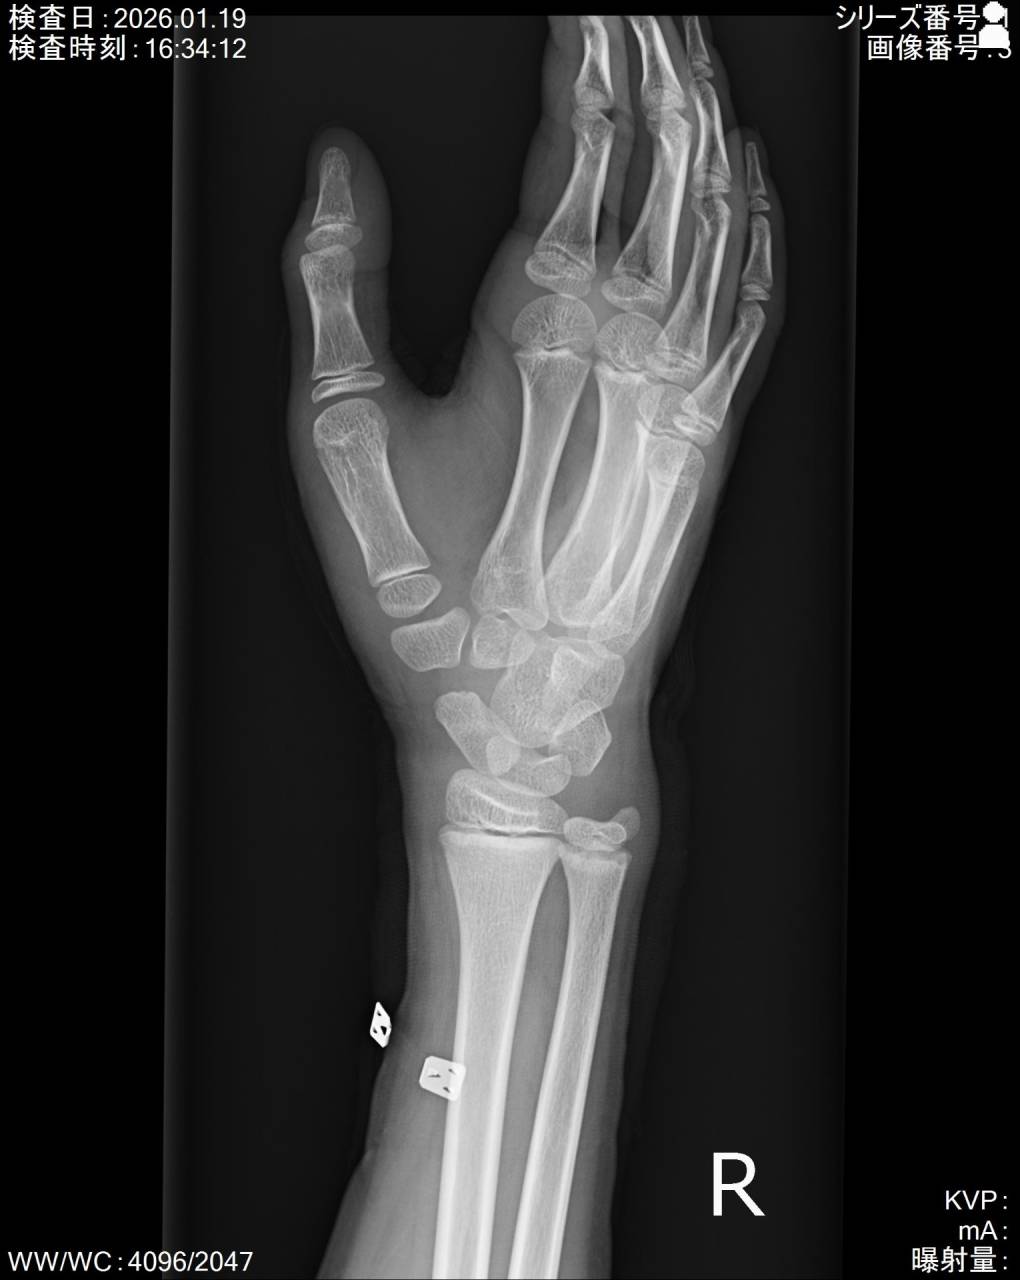

撮影した画像を確認すると舟状骨近位部に骨折がありました。

この部位は血管の走行から癒合しづらい部位でもあるので慎重に進めていかなければいけません。

癒合しづらい要因として血管の走行があります。

骨を修復するのに重要な栄養血管の血流が悪い部位なので、偽関節や無腐性壊死を引き起こす恐れがあるので注意が必要です。